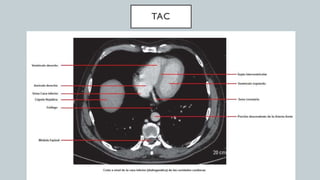

El documento detalla la anatomía del corazón y su ubicación en la caja torácica, incluyendo estructuras como las aurículas, ventrículos y arterias. También se abordan técnicas de diagnóstico por imagen, como radiografías y TAC, para visualizar la morfología cardíaca. La información está dirigida a estudiantes de medicina y profesionales interesados en la anatomía cardíaca.